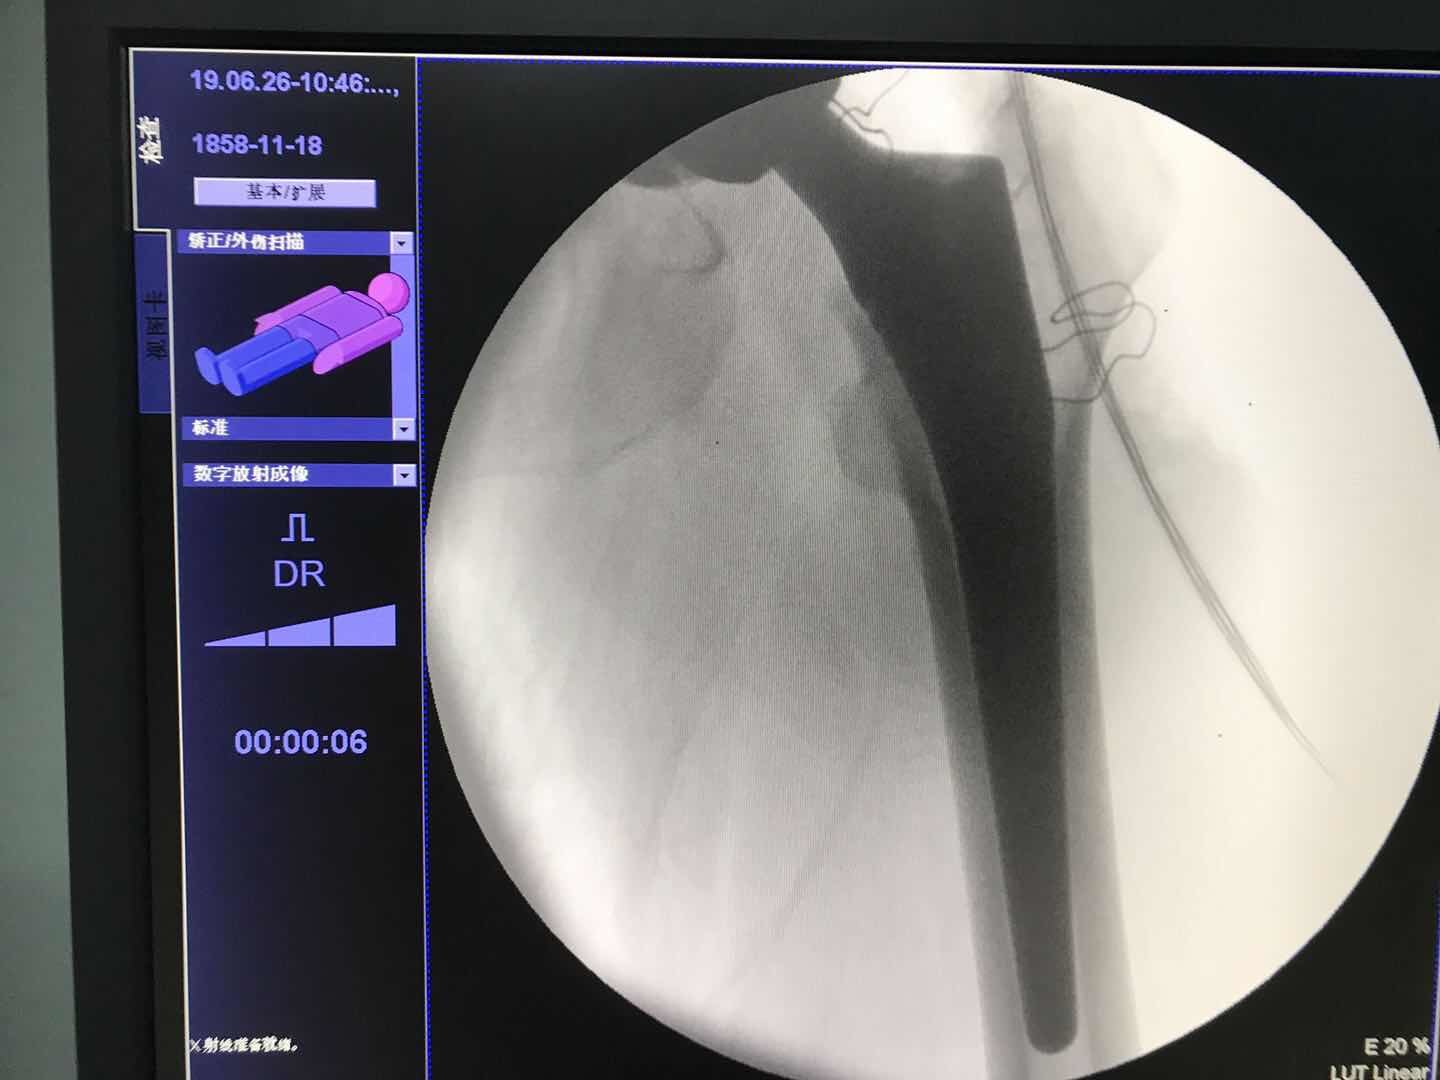

該手術使患者可以盡量用保髖治療的方法使用自己的關節,盡量推遲人工關節的置換自1997年,擅長:成人發育性髖關節發育不良、DDH人工關節置換術、運動醫學。號販子電話,圈子口碑最好100%有號!我科張洪教授率先在我國開展髖臼周圍截骨手術治療成人髖關節發育不良已經完成手術1000余例,大大提高了患者的生存質量,為患者帶來福音下圖為一位雙側髖關節發育不良患者,先做了癥狀較重的一側同一患者,術后。